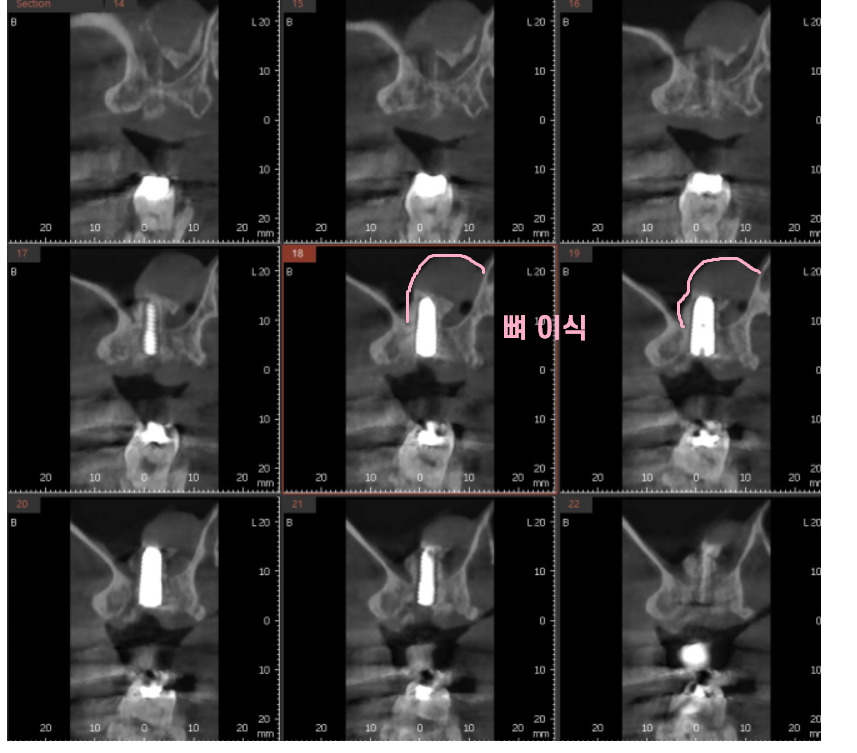

ct속 문제의 치아

뼈가 내려가다못하여

뿌리 염증까지 심해져서

이제 시기가 되었습니다.

놓아줄 시기가 되었다는 뜻이죠ㅠㅠ

24.01.16

오른쪽 아래 임플란트 치료가 끝나자마자

왼쪽 강동구 임플란트 식립하였습니다.

잇몸뼈 내려감

뿌리 염증

2가지 원인으로 잇몸뼈가 많이 없었는데요.

깨끗하게

염증을 제거하고

부족한 뼈를 이식하여 치료를 진행하였습니다.

24.02.16

동그랗게 뼈가 올라간 것이

잘 보이시죠~?